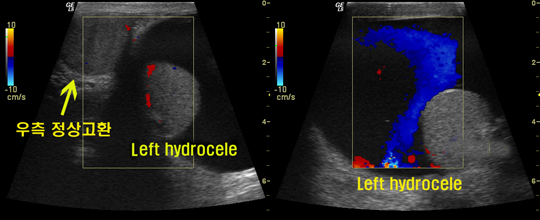

-혹부리 영감의 혹, 그 안에는 무엇이 있을까? 부풀어 오른 혹을 턱 밑에 간직한 혹부리 영감. 착한 혹부리 영감이 도깨비를 만났을 때 혹을 노래주머니라고 속여, 도깨비에게 혹을 떼어 주고 위기에서 탈출했다는 내용의 동화는 어릴 적 한 번 쯤 들어본 이야기이다. 헌데, 혹부리 영감의 혹이 얼굴이 아닌 고환에 달렸다면 어땠을까? 현대에 이러한 증상으로 비뇨기과를 찾는 남성들이 있다. 이유인 즉 슨, 고환이 어느 날부터 부풀어 오르기 시작한 것이다. 대부분의 남성들은 그것이 별로 불편하지 않을 때 까지는 이를 방치했다. 하지만 이러한 증상은 방치할수록 점차 심각해졌다. 부풀어 오른 고환의 크기가 점차 커진 것이다. 이렇게 고환이 커지면 걸을 때는 물론 가만히 있어도 불편하게 된다. 또한 점차 커지는 음낭으로 인해 음낭 속에 음경이 묻히는 증상까지 발생할 수 있다. 커진 음낭 때문에 그 무게를 견디지 못하고 견인통이 생기거나 심한 경우에는 정상적인 성생활에도 지장을 줄 수 있어 일상생활에서 겪는 불편함이 많다. 이러한 증상은 의학적으로 ‘음낭수종’이라 한다. 전문가들은 음낭수종이 의심되는 고환이 부풀어 오르는 증상이 있다면 전문의를 찾아 검사를 받아볼 것을 권한다. 강남J비뇨기과(강남제이비뇨기과) 박천진 원장은 검사 결과 음낭수종이라면 조속한 치료가 필수라 조언한다. 음낭수종은 음낭이나 고환의 염증은 아닌지, 장이 밀려들어와 있는 탈장이 아닌지 의심해 볼 수 있는데, 경우에 따라서는 고환염이나 부고환염, 종양 때문에 음낭수종 증상이 발생되기도 한다. 이러한 경우를 제대로 판별하여 그에 맞는 치료를 해야 하는데, 이를 위해서는 해당분야의 전문의에게 세심하고 자세한 검사인 ‘음낭컬러 도플러 초음파 검사’를 받아 확실한 치료 방법을 계획해야 한다. 보통 ‘바늘로 콕 찌르면 해결되지 않을까’ 라고 생각할 수 있다. 물론 이런 경우도 있다. 주사기를 이용해서 물을 뽑아내는 것이다. 하지만 이것은 다시 증상이 재발하기 때문에 보다 전문적인 수술 방법을 택하는 것이 좋다. 즉, 음낭수종은 자연치유가 되길 바라다가는 더 크게 악화되는 결과가 나타나므로 반드시 전문의를 찾아야 하며, 단순히 물을 제거하는 시술보다는 철저한 검사를 통해 간단하게 제거를 하는 외과적 수술 방법으로 시행하는 것이 좋다. 강남J비뇨기과(강남제이비뇨기과) 박천진 원장은 “최근 음낭수종은 레이저를 이용해서 시술하고 있다. 제거해야 할 부위인, 고환막 내의 액체 분비 조직을 레이저를 통해 절개하면 보다 간단히, 출혈을 최소화한 상태에서 제거할 수 있기 때문에 부담이 줄어들었고, 수술 시간도 20분 내외로 일상생활의 지장이 거의 없다.” 며 “무엇보다 좋은 것은 수술 후에 재발할 위험을 현저하게 낮출 수 있다는 점”이라고 전한다. 레이저 음낭수종 수술은 국소마취로 간단하게 이루어진다. [OSEN=생활경제팀] osenstar@osen.co.kr 강남J비뇨기과 제공 온라인으로 받아보는 스포츠 신문, 디지털 무가지 OSEN Fun&Fun, 매일 3판 발행